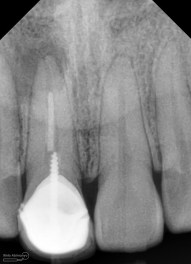

Kondisi awal saat pasien datang

dan saya lebih terkejut ketika melihat foto ronsennya

ini dia ronsen nya….

dari ronsen ini terlihat saluran akar belum diisi dengan baik, kemudian juga ada pasak ulir yang tidak ada retensi sama sekali… di ujung apeks ada gambaran radiolusensi…